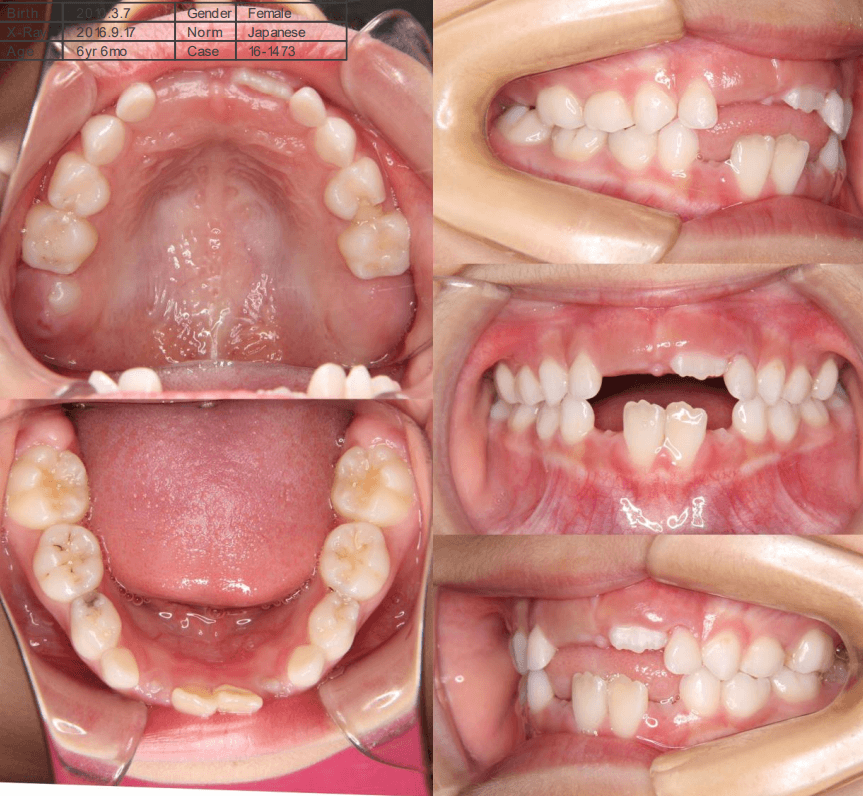

早期矯正治療 開咬症例

主訴 | 前歯がしっかり噛み合わず、食事時に違和感を覚えて来院された患者様です。 |

---|---|

診断結果 | 6歳6か月の女児。 上下の前歯が接触せず隙間があり、開咬と診断されました。 |

治療内容 |

|

治療後の経過 | 1年11か月間の動的治療により、前歯の噛み合わせが改善されました。現在は3〜4か月ごとに定期検診を行い、上下顎の骨の成長や永久歯の萌出状況を確認しながら、本格矯正治療のタイミングを検討しています。 |

治療期間 | 動的治療期間:1年11か月 治療回数:18回 |

治療費用 | 400,000円(税別) |